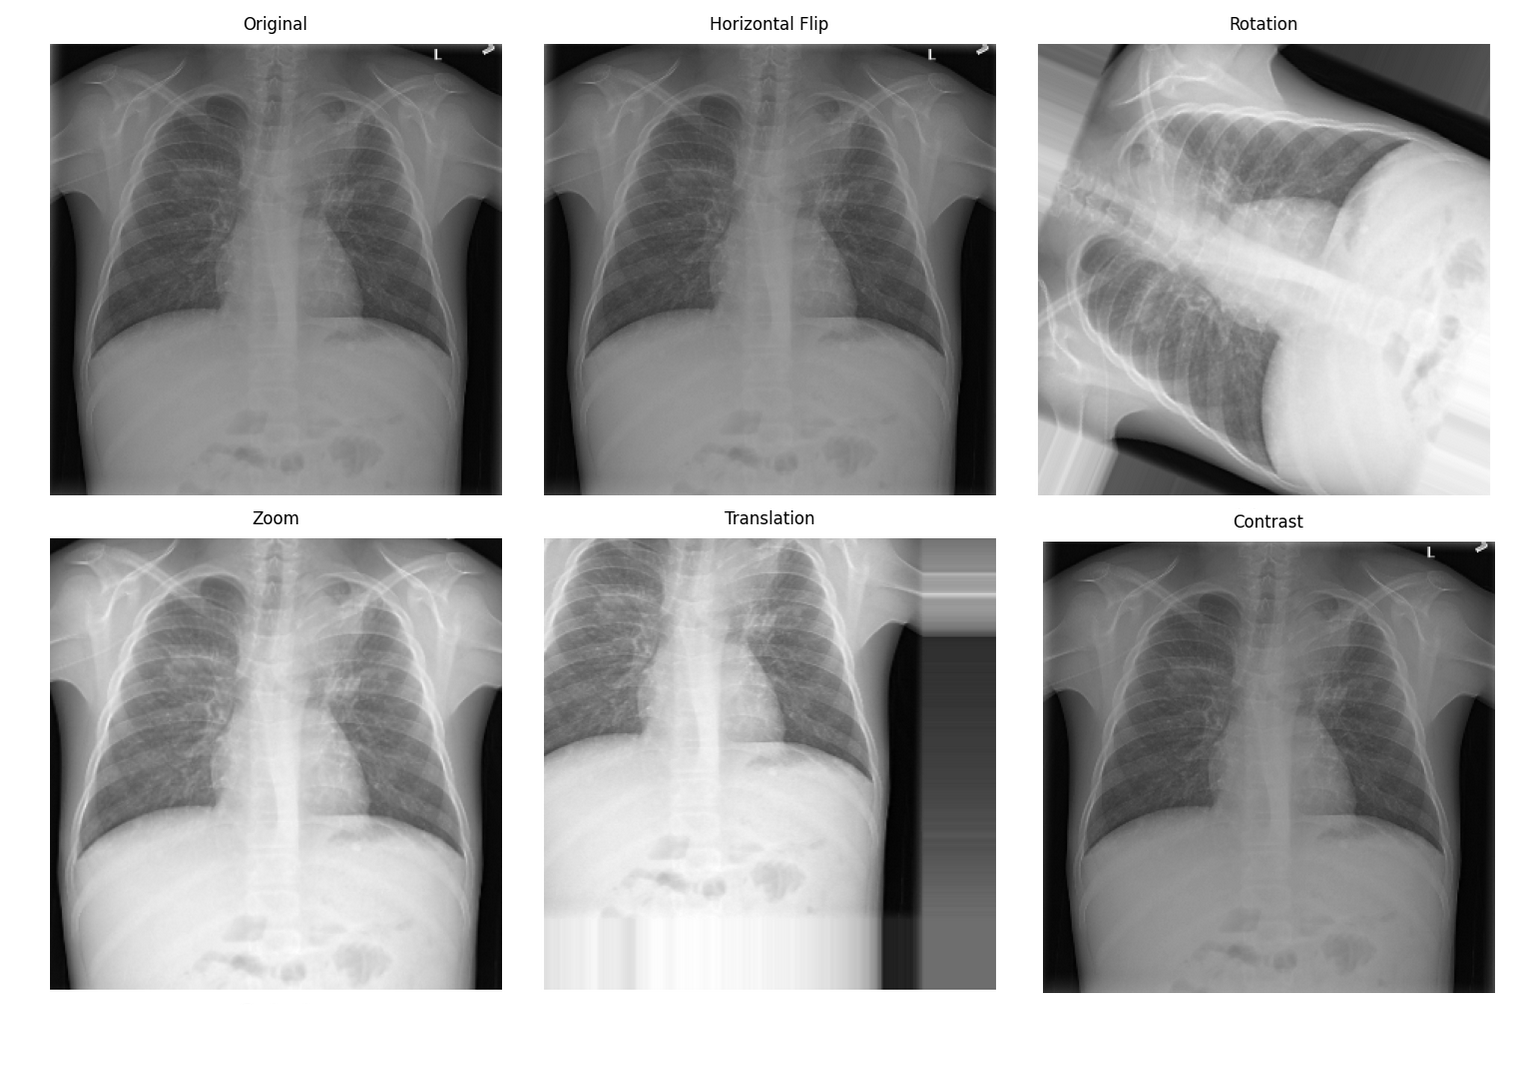

医学影像数据增强效果:从左到右依次为原始图像、旋转、弹性变形、亮度调整

医学影像数据增强的特殊性

医学影像数据增强需要考虑:

- 解剖合理性:增强后的图像必须保持解剖学正确性

空间变换增强